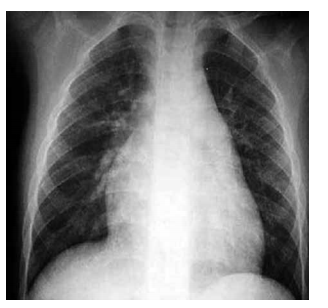

Homem, 35 anos, apresenta os seguintes achados: ventrículo direito palpável, sopro sistólico em borda esternal esquerda alta e desdobramento fixo de segunda bulha. Eletrocardiograma: bloqueio de ramo direito. A radiografia de tórax está ilustrada a seguir.

O diagnóstico é compatível com